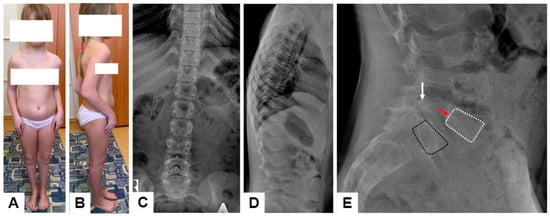

It is interesting to note the clinical features of an 11-year-old patient, characterized only by contractures without fractures (F14-P15) (Figure 5). At birth, she was found to have bilateral clubfoot and flexion contractures of the elbow joints, for which the Ponseti method (casting and Achilles tenotomy), arm casting (bar with hinges), and reconstructive foot surgeries at ages 3 and 5 were applied. To date, the girl has not had any fractures. Upon examination, the patient’s height was −0.72 SD, body weight −0.11 SD, and head circumference 0.32 SD, and flexion contractures of the elbow joints was as follows: right extension to 110 degrees, left to 100, and flexion to 40 degrees (active and passive). The hands were in palmar flexion position, actively corrected to dorsal extension. The right foot was in a neutral position, the left in equino–cavus–varus. Radiological features included positional thoracolumbar kyphosis with normal height and shape of the vertebral bodies and intervertebral disc (Figure 5C,D). Asymptomatic spondylolytic spondylolisthesis of L5 was revealed on the lateral radiographs (Figure 5E).

Figure 5. Appearance of the patient F14-P15 with AG-like phenotype (A,B). X-rays of the spine in frontal and lateral projections (C,D). Lateral radiographs of the lumbosacral region of the patient with spondylolytic spondylolisthesis: spondylolysis of the L5 vertebral arch (white arrows) and anterior displacement (red arrows) of the L5 bodies (white dotted lines) in relation to the S1 (black dotted lines) (E).